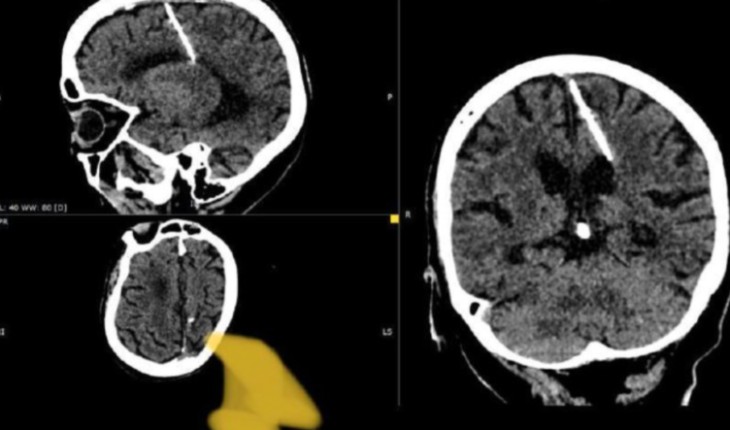

Uma mulher idosa na Rússia descobre ter uma agulha de 3 cm no cérebro após exame de tomografia.